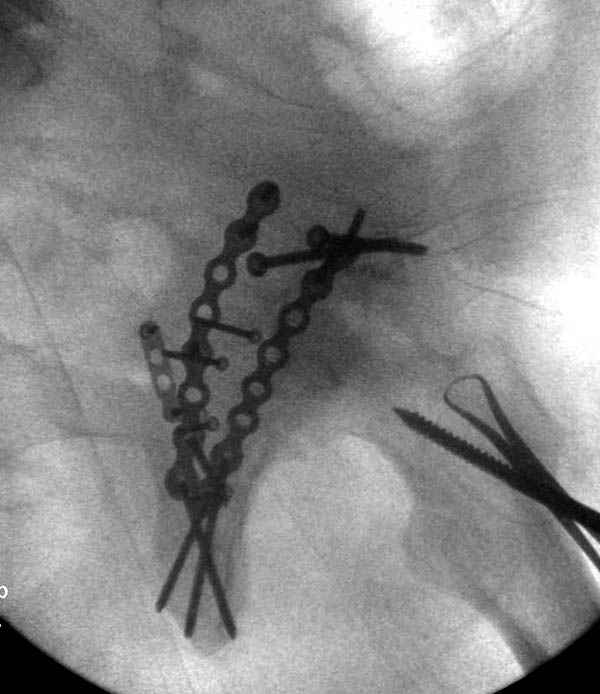

Прооперирован вчера на 13 день после поступления.

Больному 41 и из-за гемодинамической нестабильности в течение первых 7 дней был в реанимации под интубационной седацией.

Кроме перелома плеча у больного старый дистракционный перелом T12-L1 оперированный когда-то и кем-то, открытый перелом костей предплечья, который был прооперирован в ночь поступления, после I&D (хирургической обработки). Из-за разрыва селезенки при поступлении травма хирургами произведено удаление.

Дополнительно имеется перелом ацетабулума: задняя

колонна с полупоперечным переломом, и переломы костей лица.

На седьмой день зафиксирован перелом ацетабулума через задний доступ. Перед операцией для профилактики DVT, IVC фильтер, также получает Lovenox.

По возможности вышлите снимки, сканы таза до

реконструкции, интраоперационные.

По снимку создается впечатление о высоком поперечном переломе, задней колонны, стенки; почему не пользовались *magic screw*?

Положение больного на животе или на боку?

Не хотелось отклонятся от основной темы, поэтому здесь краткие ответы..

Латеральное положение облегчает проведение тракции через вертел, за 5 мм стержень за вертел (грузом через тракционное приспособление), на обычном рентгенопрозрачном операционном столе, а для положения на животе, наверное, Judet Table более приемлем, потому что там имеется латеральное тракционное устроиство.

Там множество обычных 2.7 мм шурупов, потом идет фиксация основными пластинами.